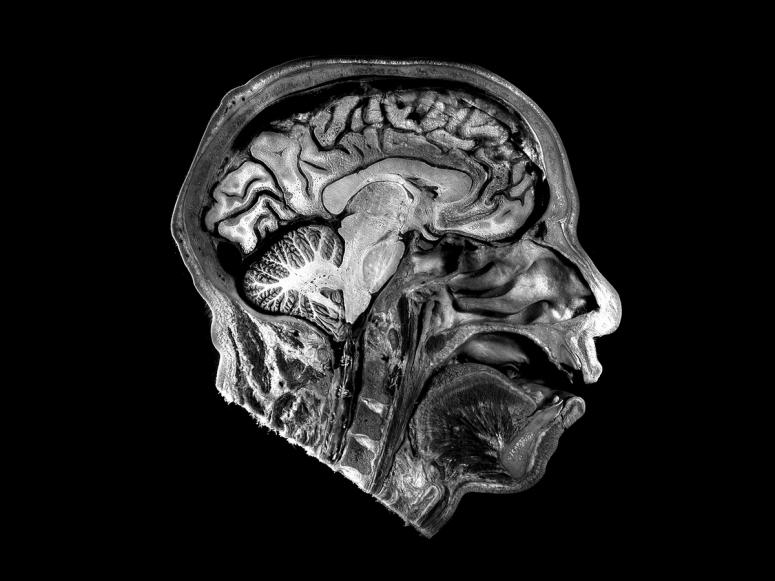

Smell is a highly individualized sense: The same odor or olfactory stimulus can trigger common, though not identical, reactions from person to person. A recent study published in the science journal Nature suggests that our diverse experiences with scent have to do with how they are encoded in the brain. “All of us share a common frame of reference with smells,” Sandeep Robert Datta, an associate professor of neurobiology at Harvard Medical School and a senior author of the paper, told The Harvard Gazette. “You and I both think lemon and lime smell similar and agree that they smell different from pizza, but until now, we didn’t know how the brain organizes that kind of information.”

A large part of that opacity stems from the difficult task of creating quantitative sample sets for odor molecules, which is much more complex than, for example, controlling variables of light to study visual perception. That’s slowly changing with new technologies. For the study, neurobiologists at Harvard used machine learning to analyze thousands of chemical structures known to have odors, detailing features such as molecular weight, electrochemical properties, and number of atoms for each one. With this data, they have begun to compare the chemical makeup of different odors to one another—as well as how a given odor correlates to neural activity in the piriform cortex and olfactory bulb, which are responsible for encoding smells. “This is the first demonstration of how the olfactory cortex encodes information about the very thing that it’s responsible for,” Datta said, “which is odor chemistry, the fundamental sensory cues of olfaction.”